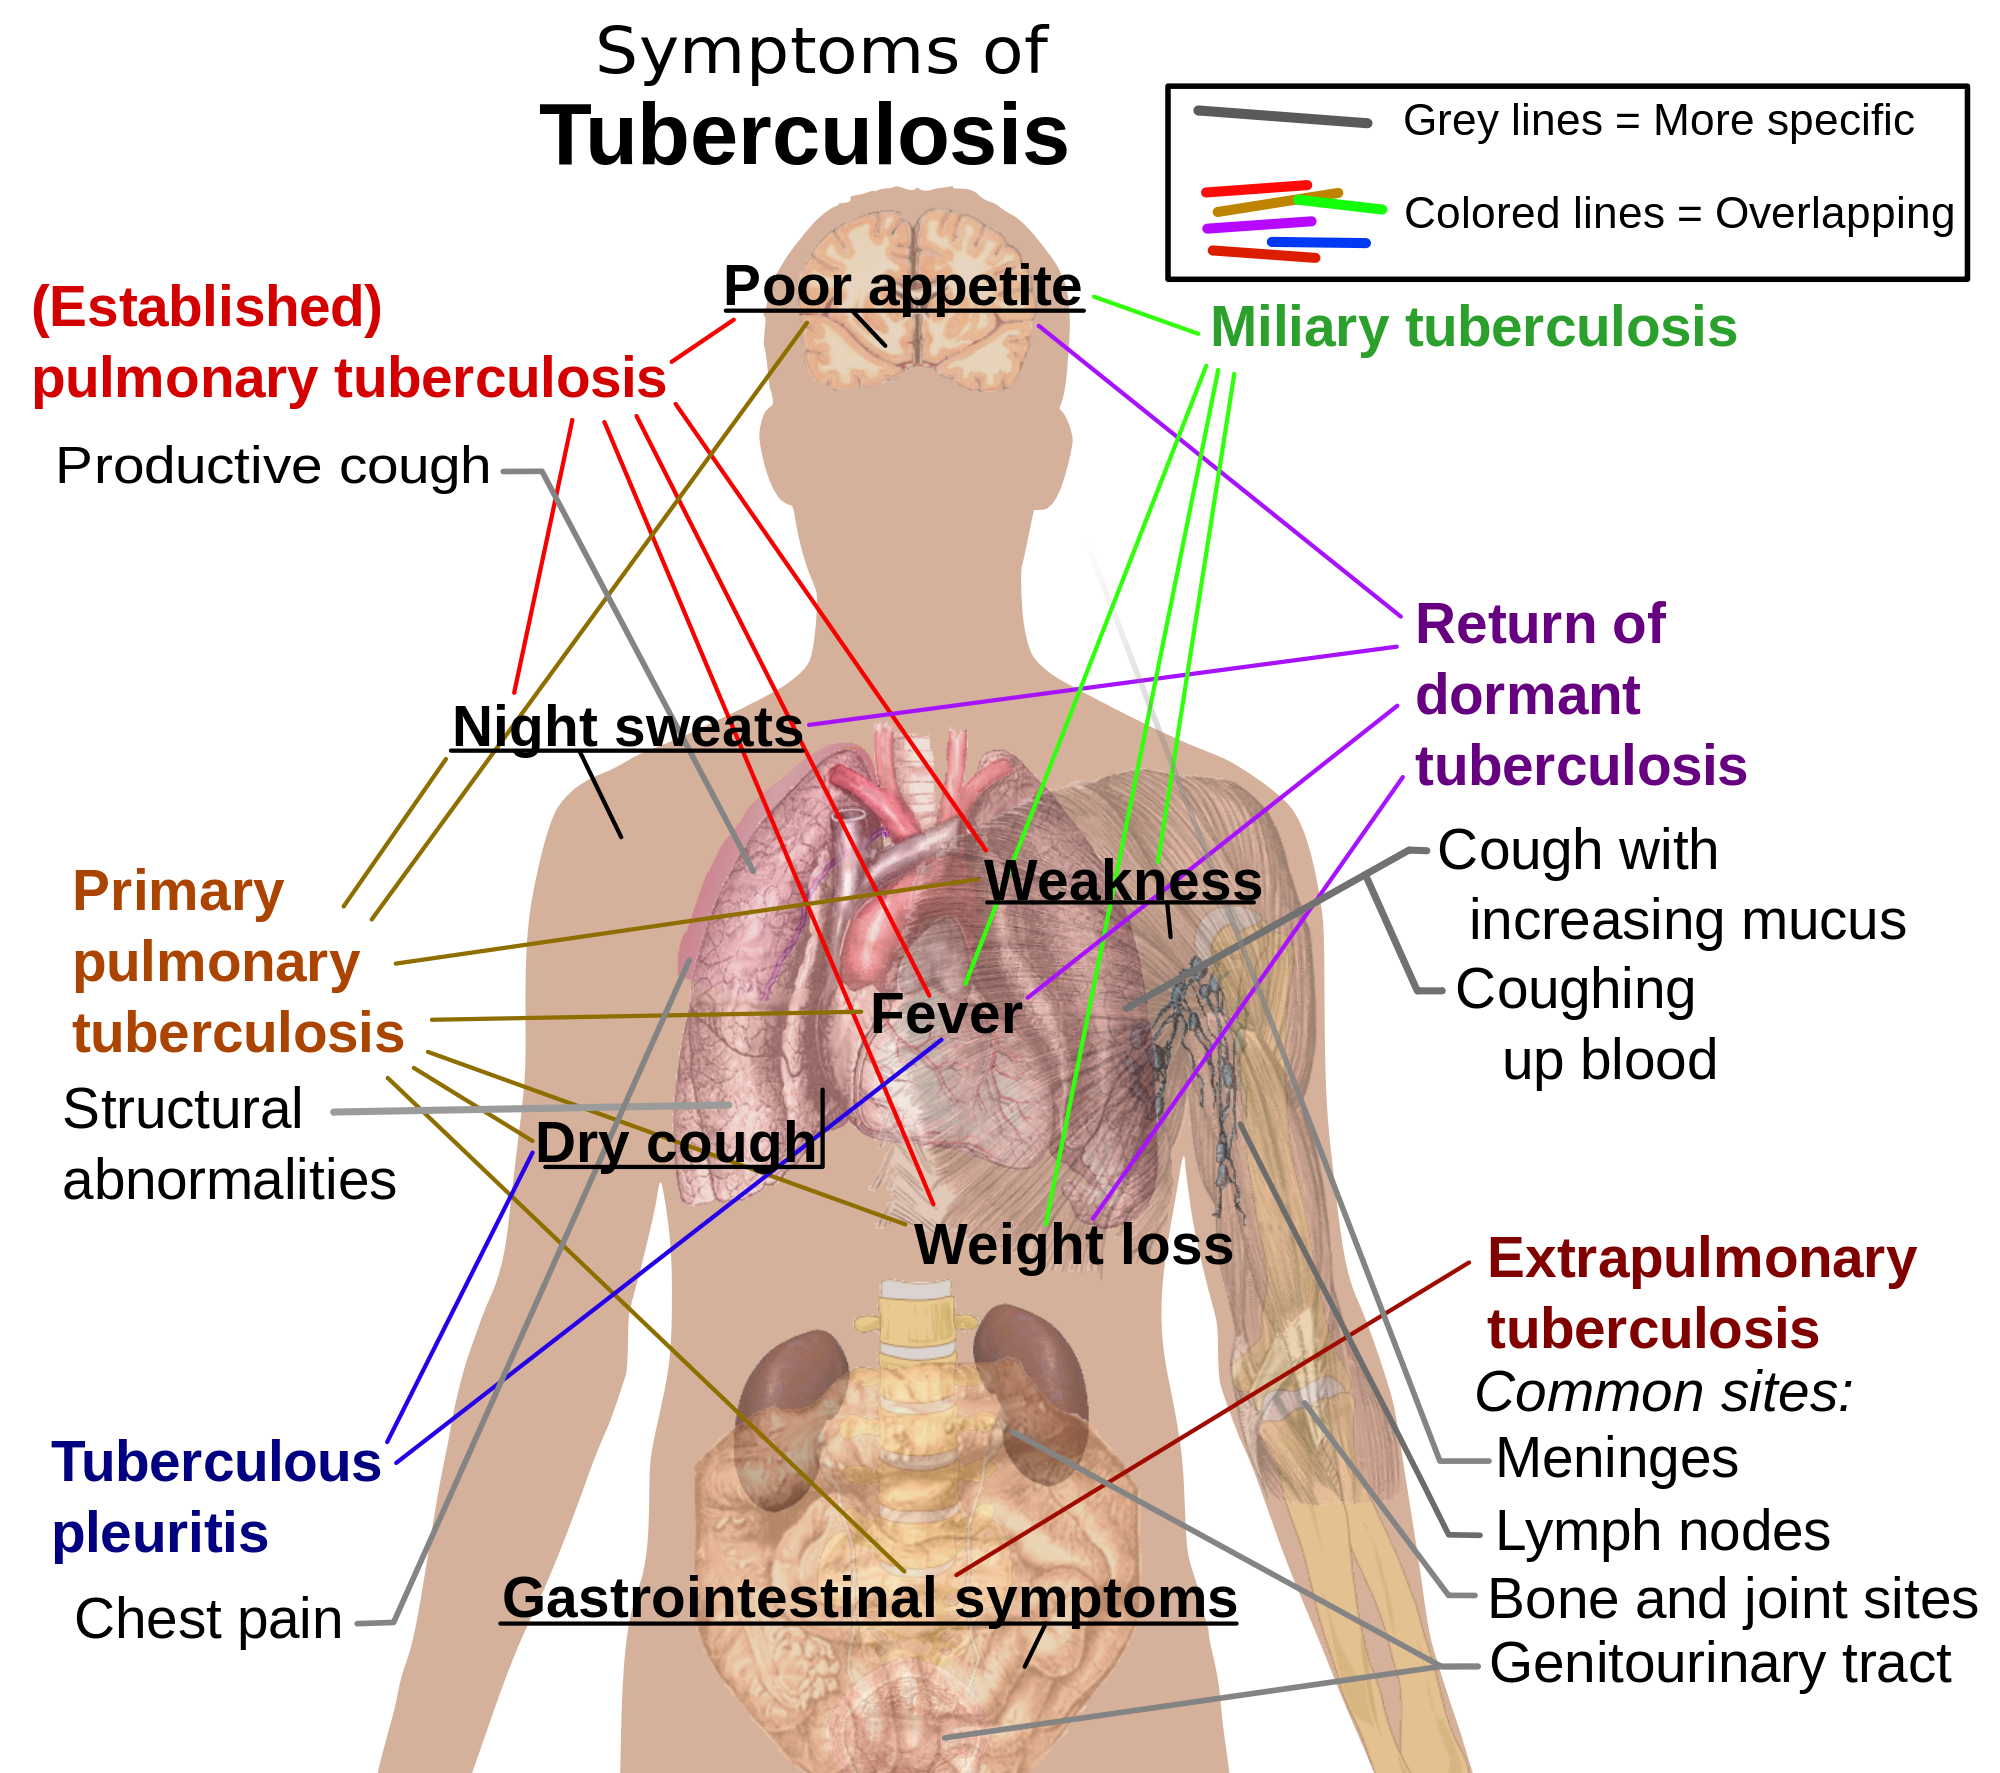

4. Pulmonary Tuberculosis:

The lungs lose their elasticity and are unable to allow gaseous exchange. It is caused by bacteria. Sufferers experience prolonged cough and pains.

4. Pulmonary Tuberculosis:

The lungs lose their elasticity and are unable to allow gaseous exchange. It is caused by bacteria. Sufferers experience prolonged cough and pains.